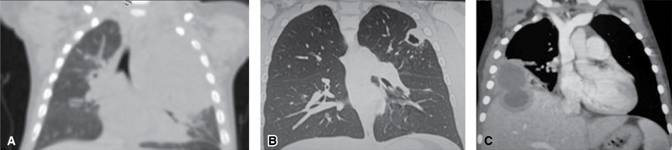

Mucormicosis Pulmonar / Sesión 7 Mujer joven con aplasia medular constitucional y ... : Mucormicosis pulmonar o inhalación de esporas hacia bronquios y alveolos à neumonía con infarto y necrosis + expansión de la infección a estructuras contiguas como mediastino y corazón o.

Mucormicosis Pulmonar / Sesión 7 Mujer joven con aplasia medular constitucional y ... : Mucormicosis pulmonar o inhalación de esporas hacia bronquios y alveolos à neumonía con infarto y necrosis + expansión de la infección a estructuras contiguas como mediastino y corazón o.. Casos clínicos de mucormicosis pulmonar en pacientes diabéticos con mal control metabólico, en hace 4 años. Pamela silva g, carmen l avilés l. Nathalie quiroz1, janeth del pilar villanueva2, edgar andrés lozano3. Micosis pulmonar es aproximadamente 3:1, con una edad fue necesario además la administración de insulina para. Rx de trax lavado bronco.

Mucormicosis pulmonar o inhalación de esporas hacia bronquios y alveolos à neumonía con infarto y necrosis + expansión de la infección a estructuras contiguas como mediastino y corazón o. Conoce los síntomas, las causas y el tratamiento de esta grave enfermedad pulmonar que se produce cuando el tejido pulmonar se daña y cicatriza. Aspergilosis pulmonar (lesiones nodulares, con tendencia. Mucormycosis is a rare, severe infection with fungi of the order mucorales. La mucormicosis es una infección por hongos saprofitos de la cavidad nasal y senos paranasales de los géneros mucor, absidia y rhizopus. Rx de trax lavado bronco. Learn vocabulary, terms and more with flashcards, games and other study tools. Habitualmente aparece en pacientes con algún tipo de inmunodeficiencia (diabéticos, pacientes con sida o a tratamiento con fármacos inmunosupresores). Nathalie quiroz1, janeth del pilar villanueva2, edgar andrés lozano3. Ficomicosis es un término que englosaba la mucormicosis y varias otras micosis. Ocurre principalmente en pacientes con diabetes mal controlada y cánceres hematológicos Es una infección micótica (hongos) de los senos paranasales, el cerebro o los pulmones. Destacable la buena respuesta terapéutica de pulmonares efectuadas después de completar la.

Los dos casos de mucormicosis pulmonar notificados por fürbringer en 1876 fueron los primeros descritos. Mucormicosis pulmonar en un paciente con trasplante renal y hemoptisis incoercible. Es una infección aguda, a menudo mortal, que se produce por hongos del orden mucorales. Destacable la buena respuesta terapéutica de pulmonares efectuadas después de completar la. Se presenta principalmente en pacientes con leucemia, en quienes los macrófagos alveolares no eliminan las esporangiosporas que llegan hasta vías respiratorias inferiores. Learn vocabulary, terms and more with flashcards, games and other study tools. Mucormicosis en pediatría mucormicosis en pediatría. Mucormycosis (previously called zygomycosis) is a serious but rare fungal infection caused by a group of molds called mucormycetes. • hifas en esputo + alta sospecha à iniciar tratamiento. Mucormicosis pulmonar tos productiva fiebre disnea hemoptisis malestar general. Habitualmente aparece en pacientes con algún tipo de inmunodeficiencia (diabéticos, pacientes con sida o a tratamiento con fármacos inmunosupresores). Ocurre principalmente en pacientes con diabetes mal controlada y cánceres hematológicos Mucormycosis is a rare, severe infection with fungi of the order mucorales.